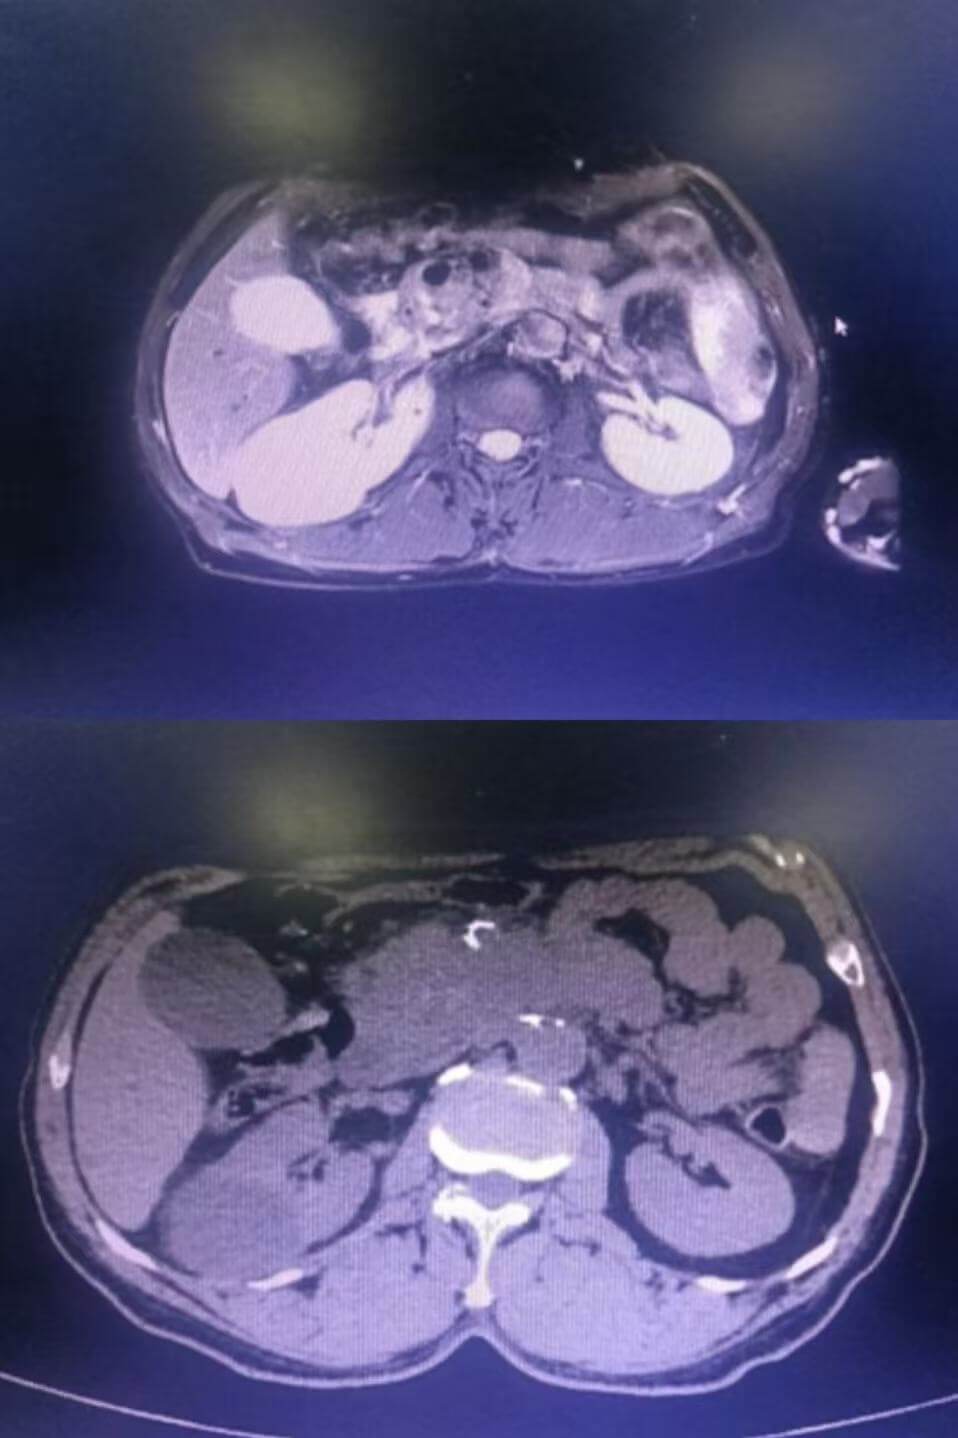

影像学检查:发现胰腺癌的“火眼金睛”

胰腺癌在腹部磁共振与腹部CT中的表现

当出现以下情况时,需警惕胰腺癌,尽早做腹部CT或MRI,必要时需要增强扫描或超声内镜进一步穿刺活检: